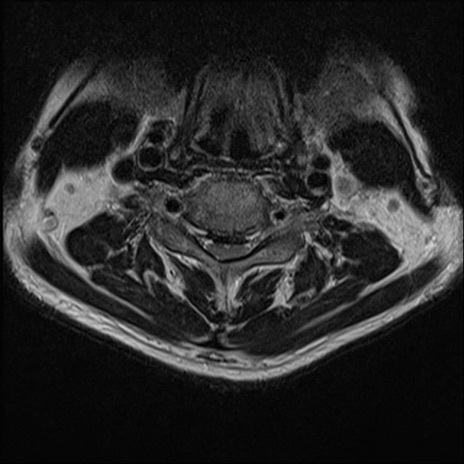

【整形】TIPS症例7 頚椎MRI T2WI(横断像)

頚椎MRI

矢状断像と横断像